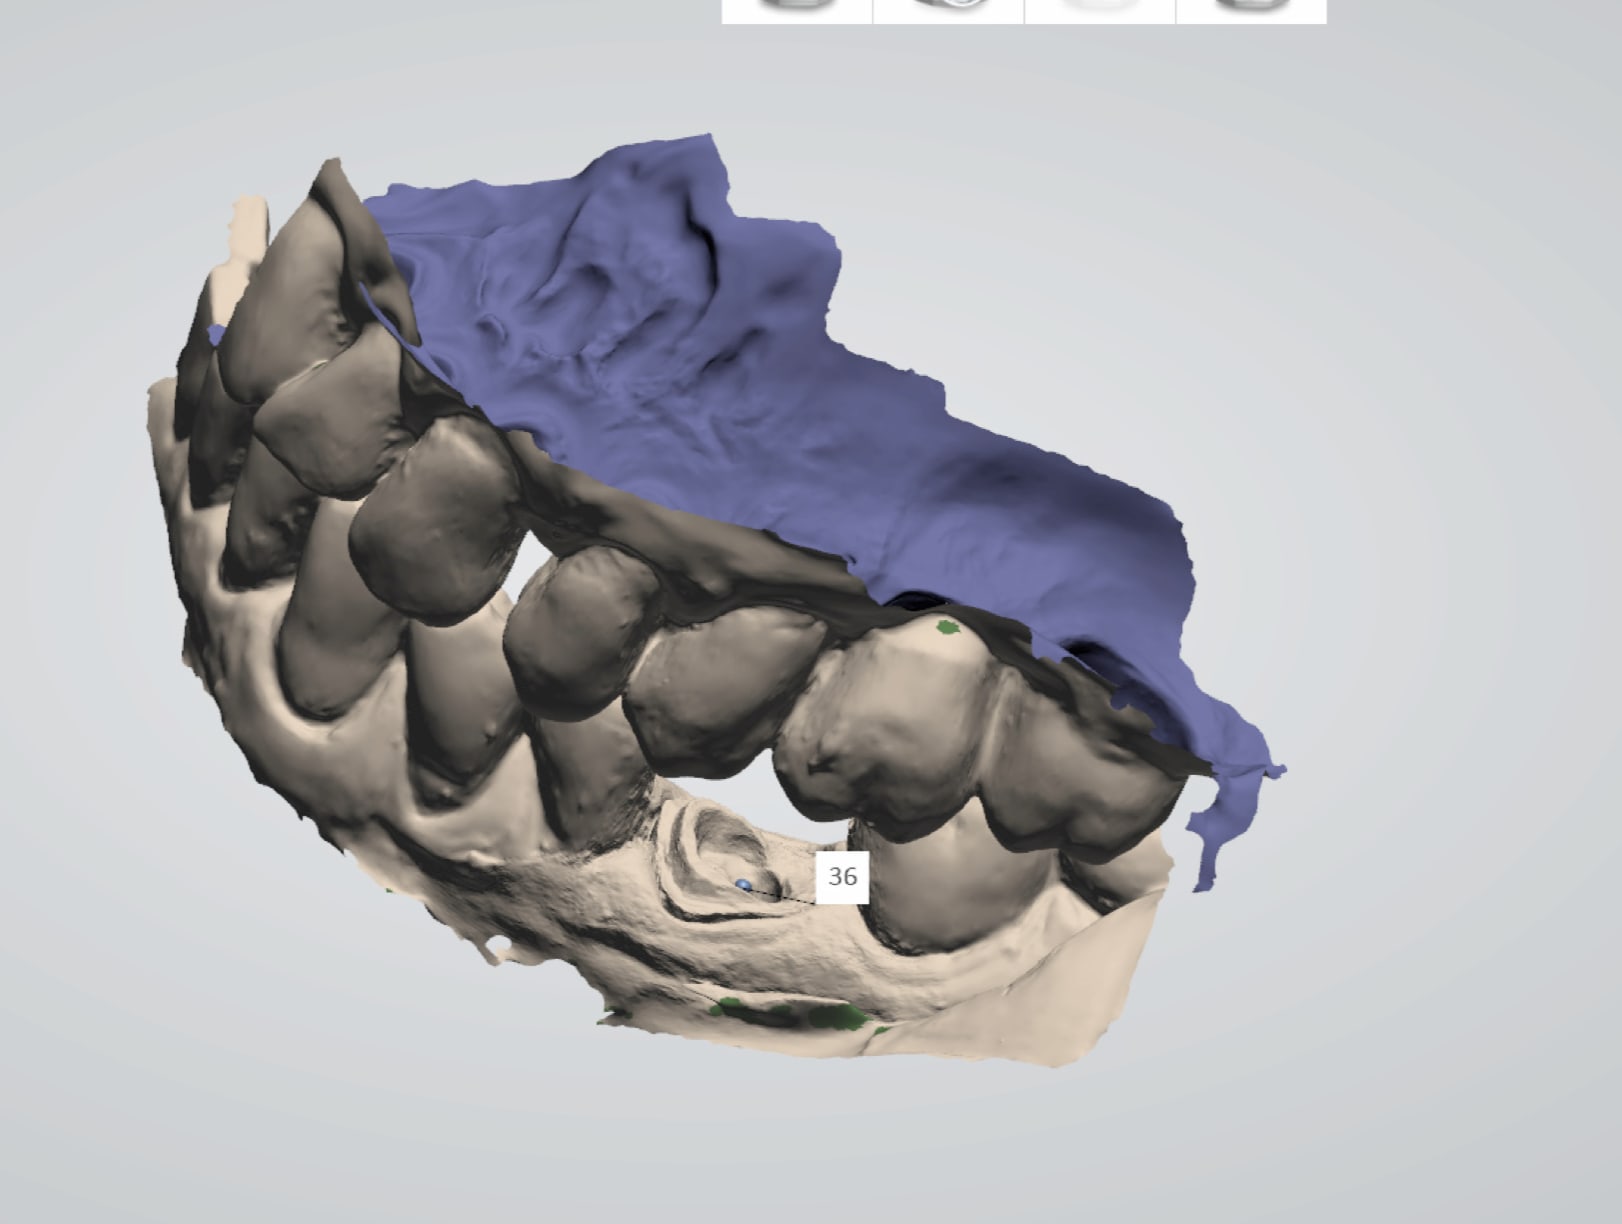

Empreinte scan post en place.

Vue platre.